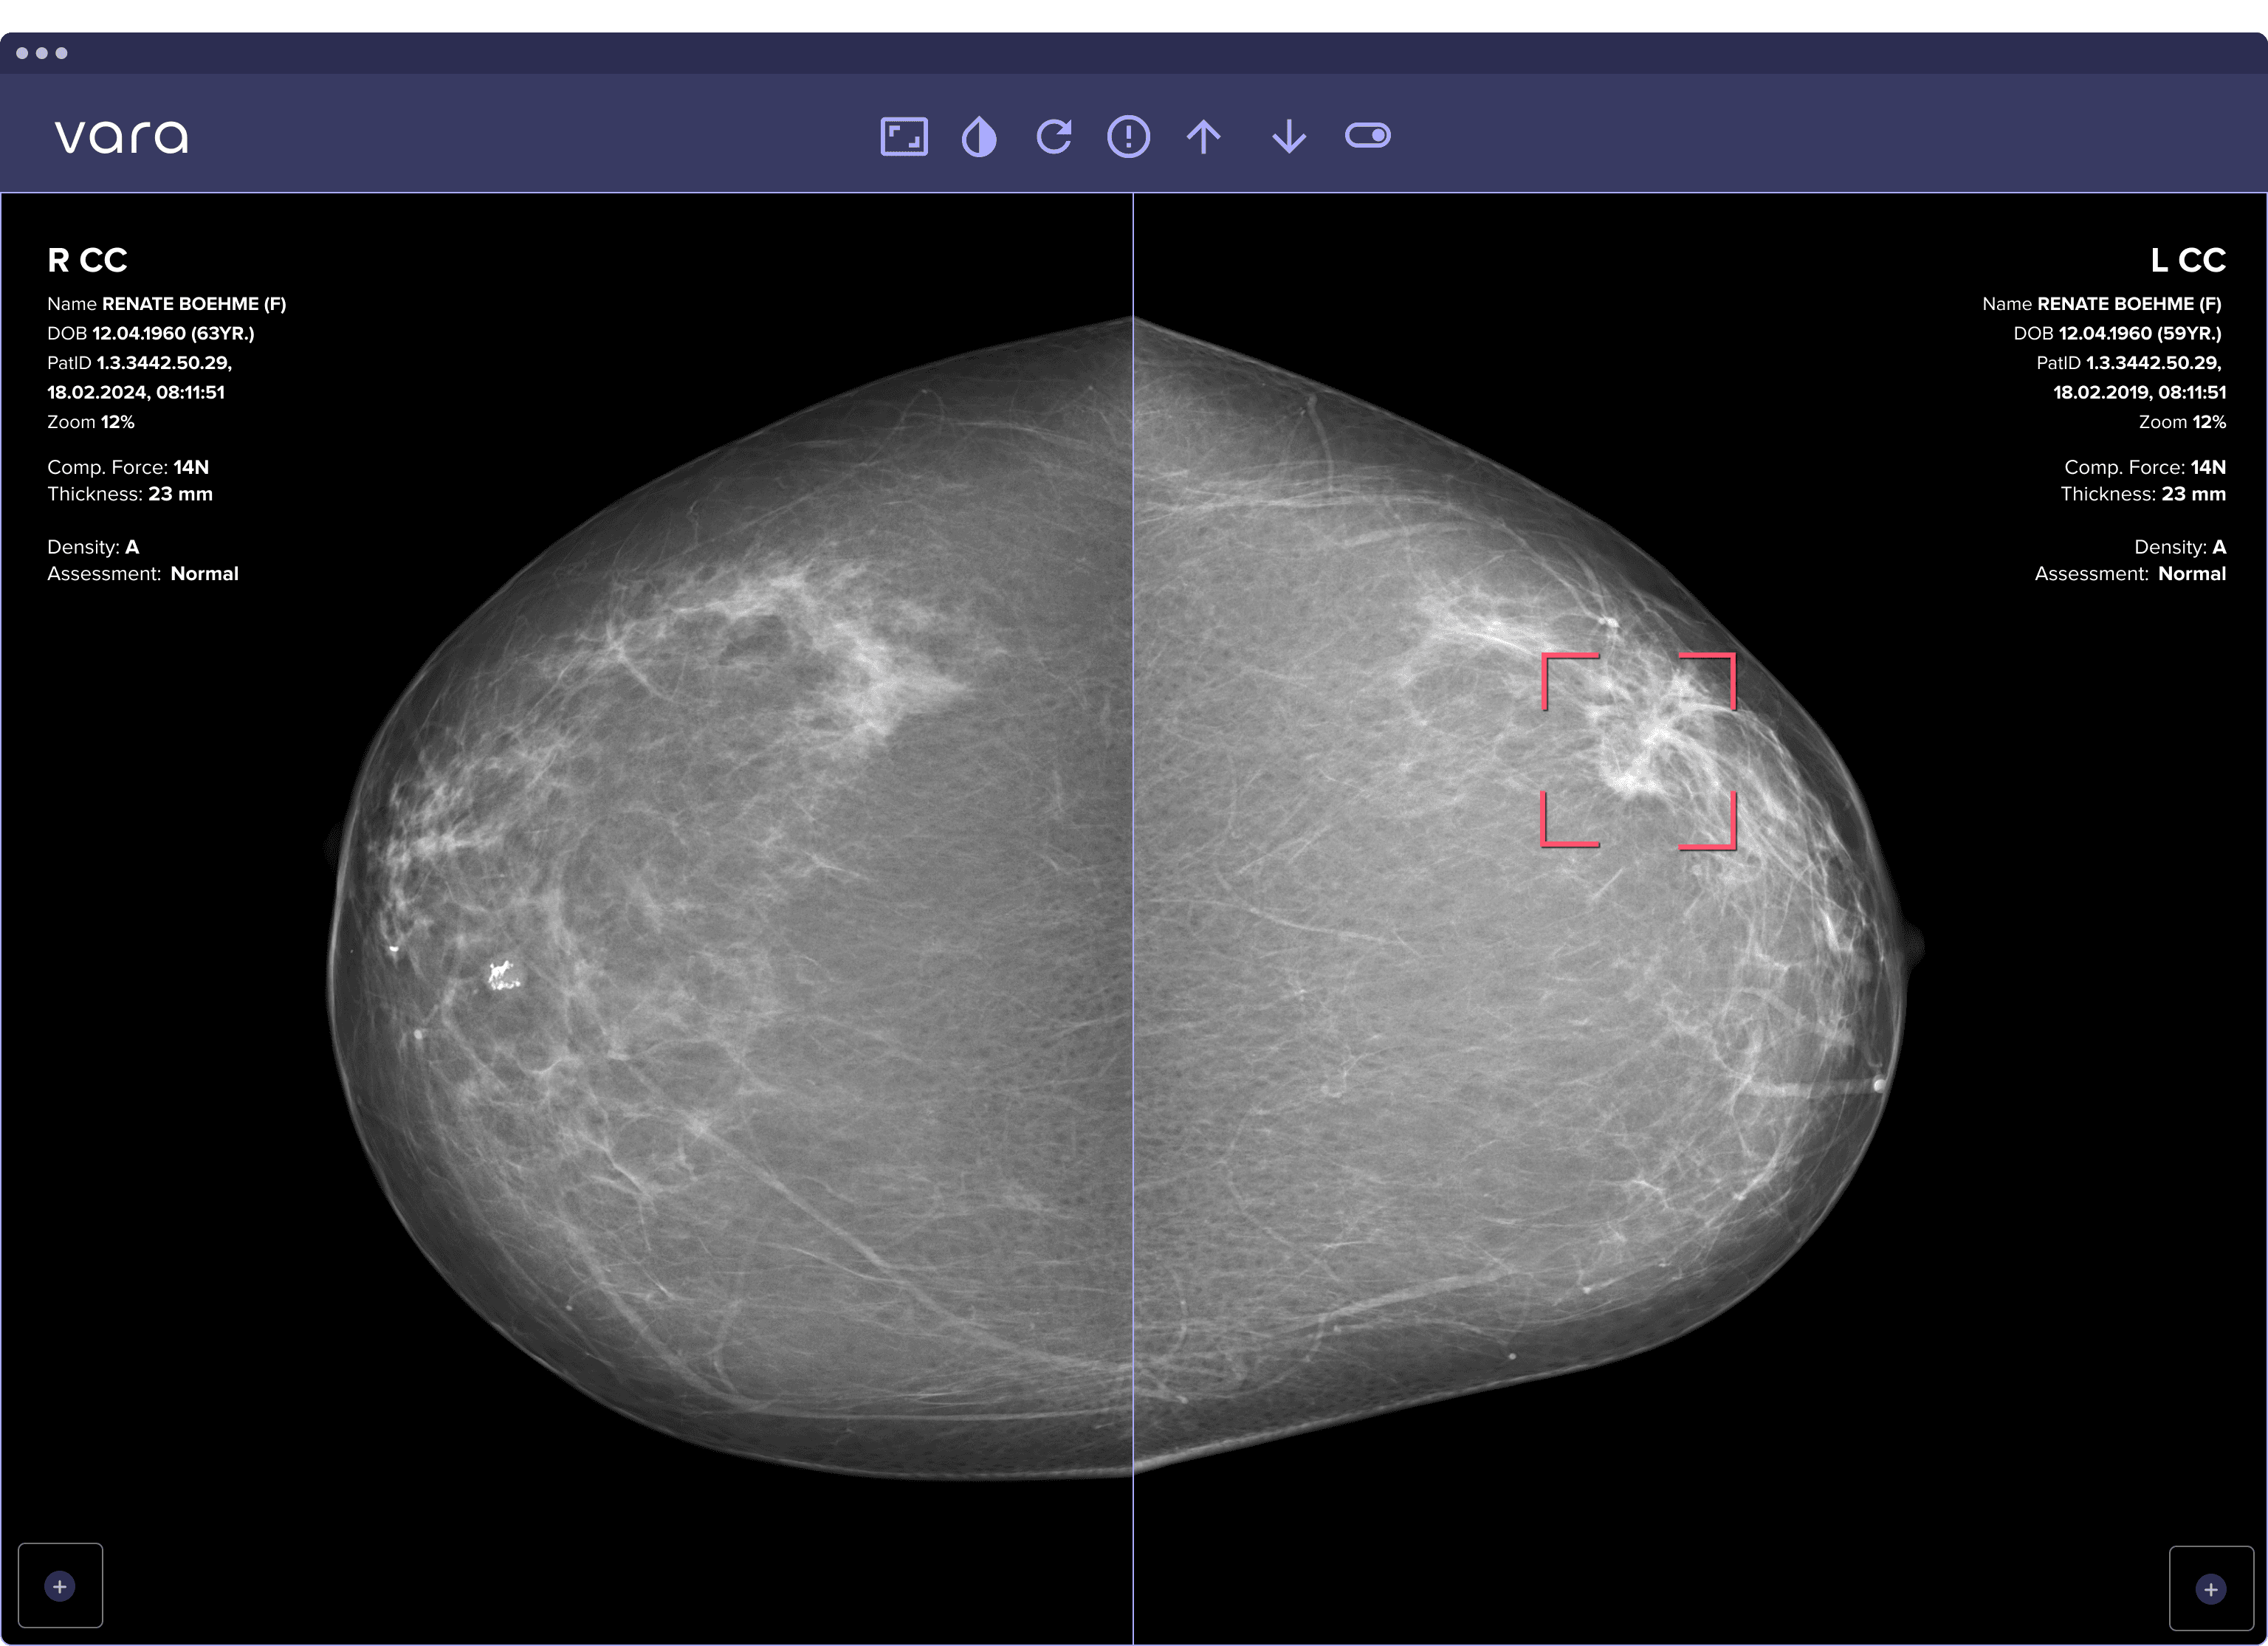

Vara Workflow

Streamline case management and prioritize reads.

Empowering radiologists with AI-driven prioritization and insights while managing screening cases seamlessly.

Safety Net

AI alerts radiologists to missed findings, reducing errors and boosting confidence in every read without bias.

Simplified Reporting

Reports for normal cases are generated automatically. Review, sign, and send in seconds.